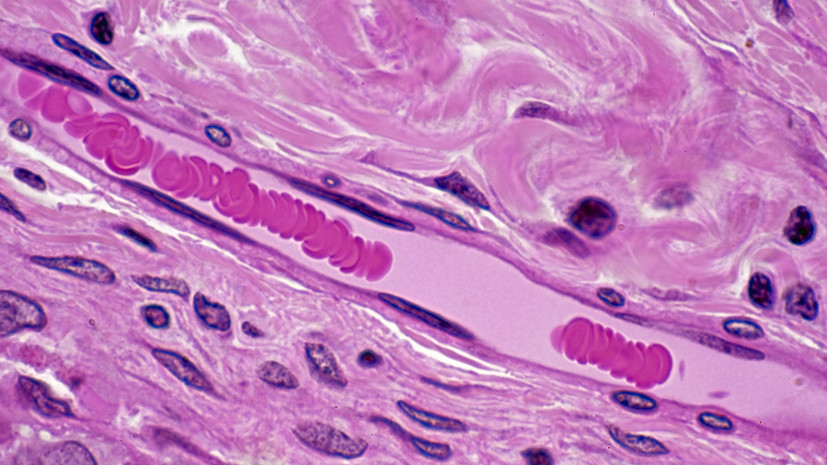

Трансфузиолог Трахтман назвал ключом к долголетию сохранение густой сети капилляров

«Исследования показывают, что аэробные нагрузки (бег, плавание, быстрая ходьба, велосипед) и силовые тренировки помогают сохранять капиллярную сеть — получающие регулярную нагрузку ткани нуждаются в кислороде и питательных веществах и «заказывают» себе адекватное кровоснабжение», — заявил он в беседе с «Газетой.Ru».